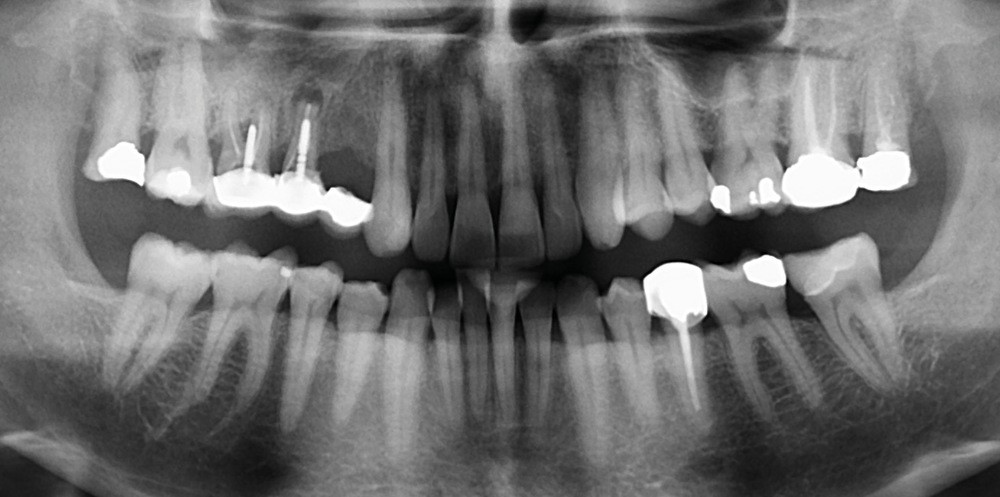

Présentation du cas clinique (fig. 1 à 3)

Le patient, âgé de 58 ans, présente un encombrement dentaire mandibulaire de 5 mm dans un contexte squelettique hypodivergent.

À la radiographie panoramique, on constate une lésion apicale sur 15 et une atteinte inter radiculaire sur 16 ainsi qu’une légère rotation de 21 sans gêne pour le patient.